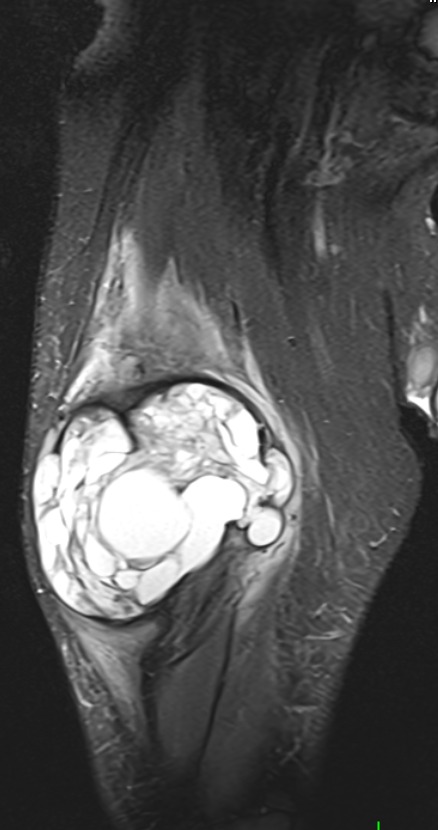

Muscle Cancer